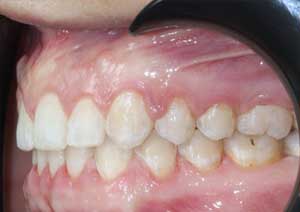

La supraclusion est définie comme le recouvrement excessif des incisives mandibulaires (inférieures) par les incisives maxillaires (supérieures).

Cliniquement, cela signifie qu’au sourire, le patient ne laisse pas apparaître les dents inférieures.

Il s’agit d’un problème de dimension verticale, fréquemment rencontré en pratique orthodontique quotidienne.

Après